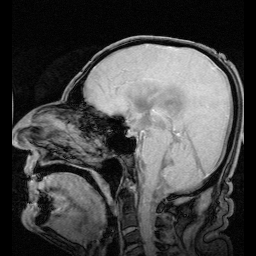

أشعة رنين مغناطيسي على المخ تُظهر تحرك السائل الدماغي الشوكي داخل الجهاز البطيني في منتصف نسيج المخ تقريبًا.